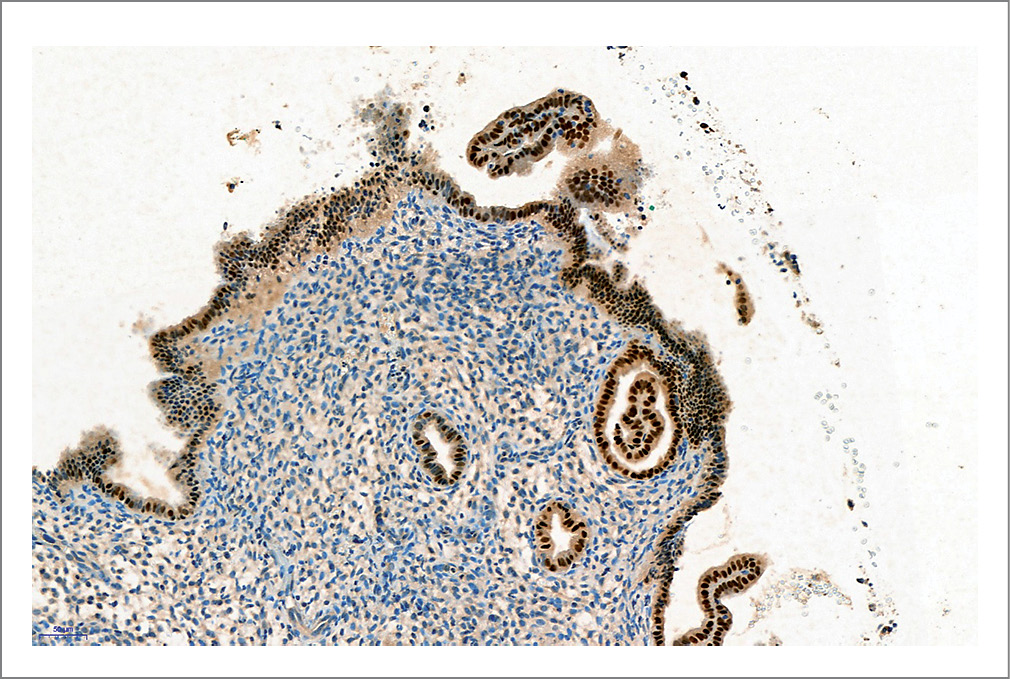

Проводили сравнительный анализ характеристик экспрессии FOX-белков в эндометрии (рис. 1–4) в соотношении с толщиной слизистой оболочки тела матки.

В группе женщин с «тонким» эндометрием достоверно чаще выявляли сниженную экспрессию FOXA2, чем у женщин из группы сравнения с нормальной толщиной эндометрия и у здоровых женщин из группы контроля (p<0,05); см. табл. 2; см. рис. 3, 4.

Рис. 3. Иммуногистохимическое исследование эндометриального образца: сниженная экспрессия FOXA2 в эндометрии (6–8-й д.п.о.), увеличение ×18,8.

Fig. 3. Immunohistochemical examination of the endometrial specimen: decreased FOXA2 endometrial expression (days 6–8 after ovulation); ×18.8 magnification

Рис. 4. Иммуногистохимическое исследование эндометриального образца: выраженная экспрессия FOXA2 в эндометрии (6–8-й д.п.о.), увеличение ×18,6.

Fig. 4. Immunohistochemical examination of the endometrial specimen: pronounced FOXA2 endometrial expression (days 6–8 after ovulation); ×18.6 magnification.